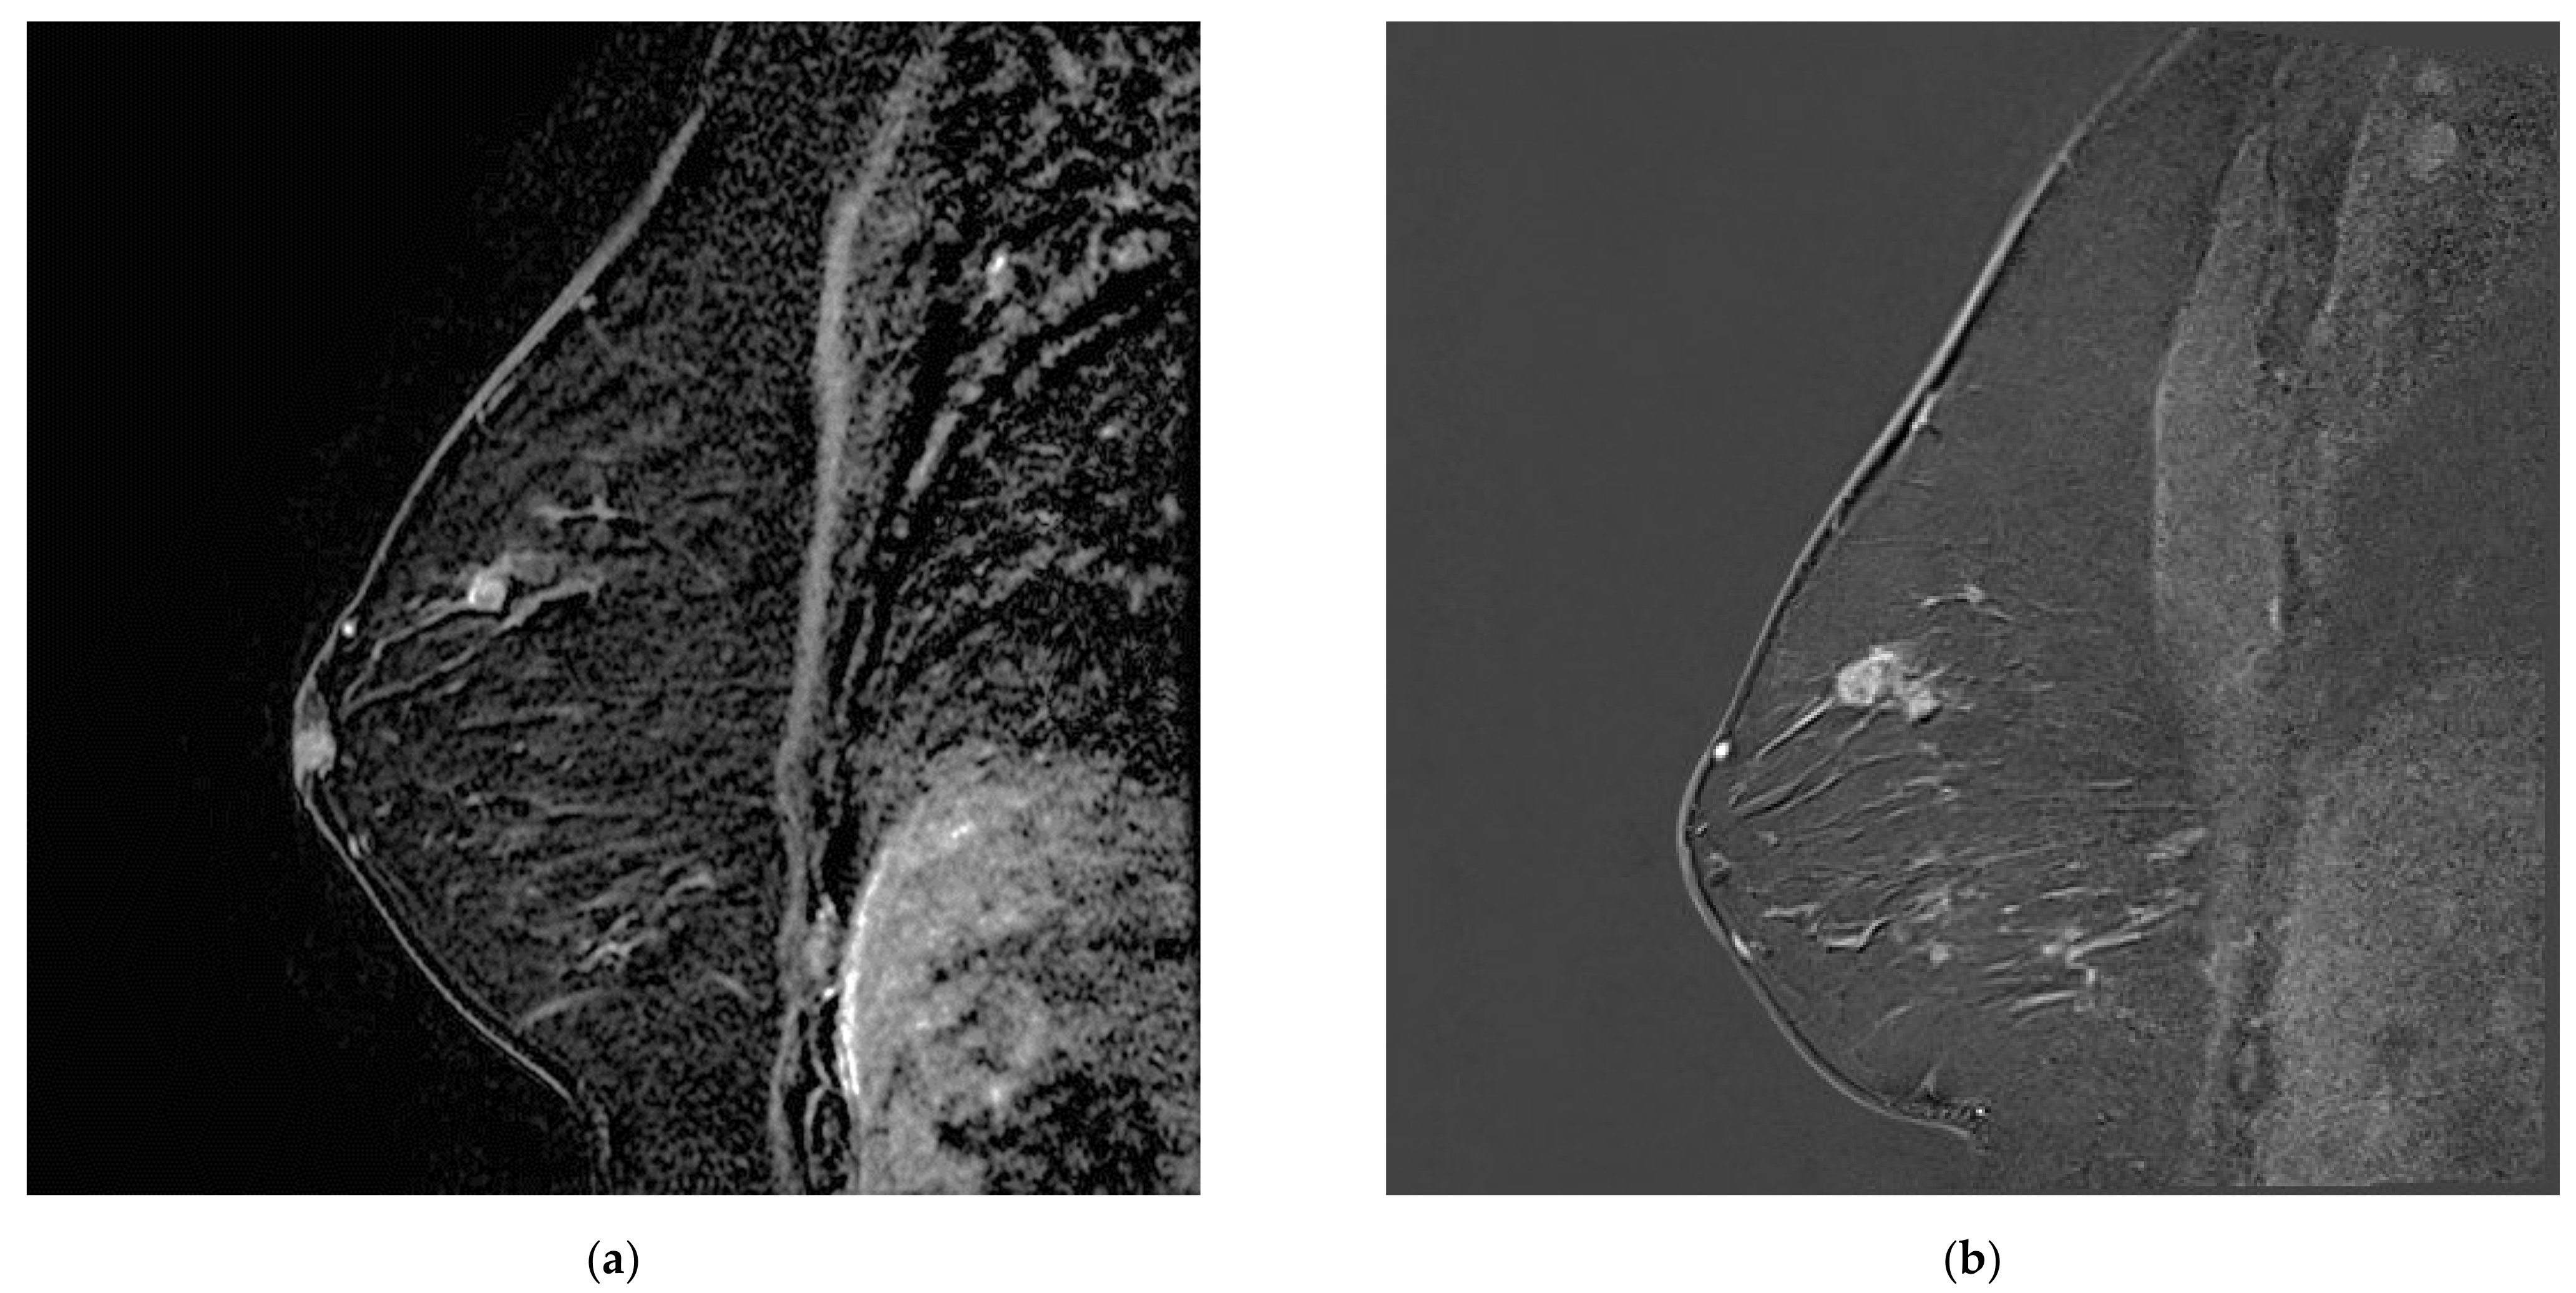

Figure 4.

Increasing breast mass in a patient known for breast papillomatosis between (a) MR A, which was misinterpreted as a papilloma and (b) MR B, corresponding to papillary carcinoma.

Figure 5.

Postoperative seroma with surrounding non-mass enhancement on MRA (a) T2-weighted sequence and (b) T1 fat sat with gadolinium. The seroma resolved and linear enhancement is seen in the same location on (c) MR B. This was initially attributed to post-surgical changes and later confirmed to correspond to disease recurrence.